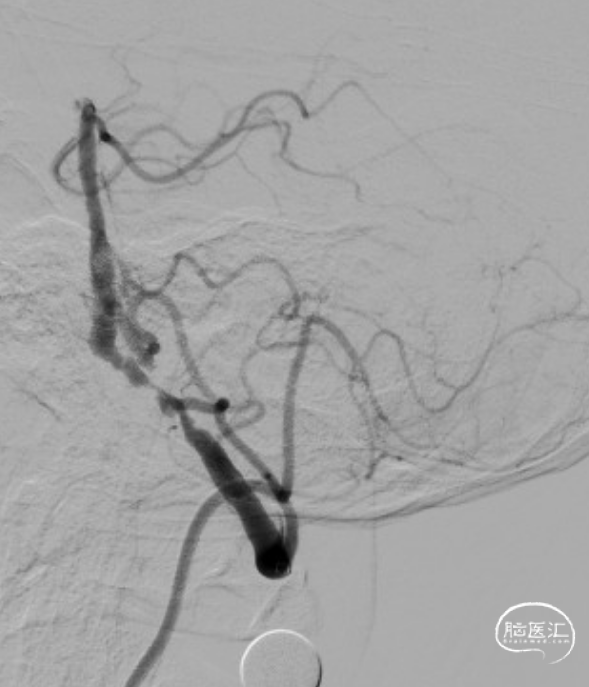

术后造影:RV4段狭窄较前明显改善。